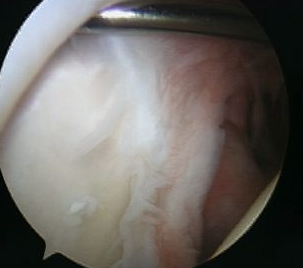

Arthroscopy

Normal insertion of superior labrum onto glenoid